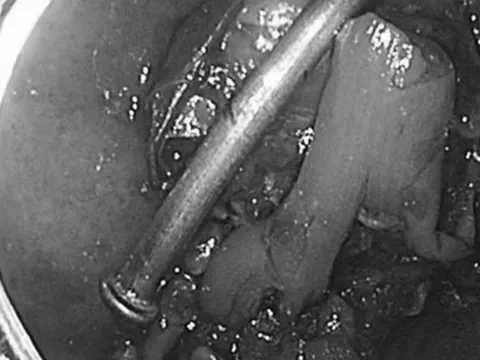

Sau khi các bác sĩ làm các xét nghiệm phát hiện việc uống cùng lúc quá nhiều nước ngọt có ga đã làm khí tích tụ trong ruột bệnh nhân. Lượng khí tích tụ quá nhiều khiến bụng phình to và gây áp lực lớn bên trong. Hậu quả là khí rò rỉ qua tĩnh mạch dẫn đến đến gan. Tình trạng này khiến gan thiếu máu cục bộ và không nhận đủ ô xy.

Các bác sĩ đã tìm cách rút khí ra khỏi ruột bệnh nhân và bảo vệ các cơ quan nội tạng khác không bị tổn thương. Xét nghiệm 12 giờ sau đó cho thấy gan bệnh nhân đã bị tổn thương nghiêm trọng. Tình hình ngày càng xấu đi. Cuối cùng, chàng trai trẻ tử vong chỉ sau 18 giờ nhập viện, theo Daily Mail.